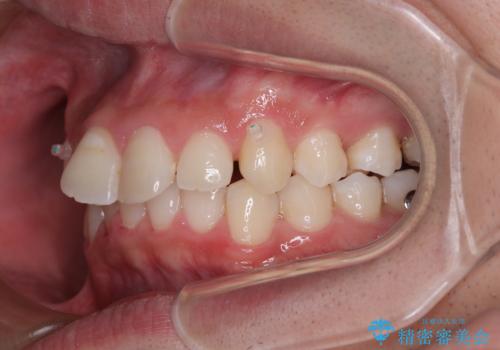

- ディープバイトと上顎前歯の突出、奥歯の咬み合わせを気にして来院された患者様です。

上顎歯列は全体的に前方位にあり、それが原因で深い咬み合わせとなり、突き上げにより上顎前歯が前方に飛び出している状態でした。

また、左右ともに上顎最後臼歯が頬側に転位している鋏状咬合となっていました。

インビザラインによる矯正治療をご希望でしたが、上顎歯列の前方位と鋏状咬合を確実に改善することを目的として、補助装置を併用することとしました。